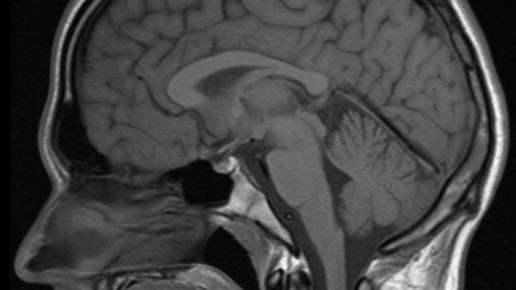

Ablagerungen im Gehirn möglich: Das Bundesinstitut für Arzneimittel und Medizinprodukte (BfArM) hat im Stufenplanbescheid vom 13. Dezember das Ruhen der Zulassungen von Gadopentetsäure-haltigen Kontrastmitteln empfohlen. Dazu zählen Magnevist und Magnograf. Grund ist die Bewertung Gadolinium-haltiger Kontrastmittel der Europäischen Arzneimittelagentur (EMA). Die Experten bestätigten, dass die Präparate, die zur MRT-Bildgebung eingesetzt werden, sich nach Injektion in geringen Mengen im Gehirn ablagern können. Die Zulassungen der intravenösen linearen Kontrastmittel mit Gadoxetsäure und Gadobensäure bleiben bestehen und sind nicht betroffen.